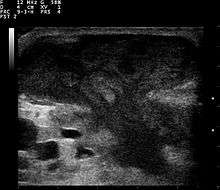

| Diagnostic method | ultrasound, CT scan[1][3] |

They are usually caused by a bacterial infection.[8] Often many different types of bacteria are involved in a single infection.[6] In the United States and many other areas of the world the most common bacteria present is methicillin-resistant Staphylococcus aureus.[1] Rarely, parasites can cause abscesses and this is more common in the developing world.[3] Diagnosis of a skin abscess is usually made based on what it looks like and is confirmed by cutting it open.[1] Ultrasound imaging may be useful in cases in which the diagnosis is not clear.[1] In abscesses around the anus, computer tomography (CT) may be important to look for deeper infection.[3]